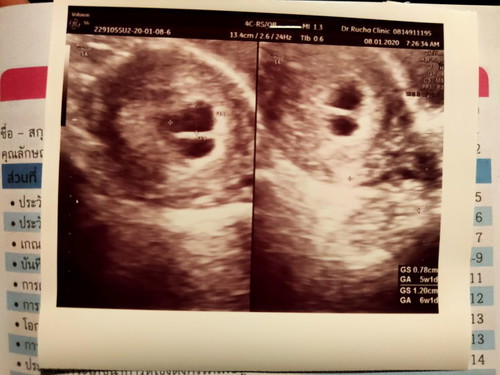

6w มี 2 ถุง ♥️♥️

มีลุ้นลูกแฝด